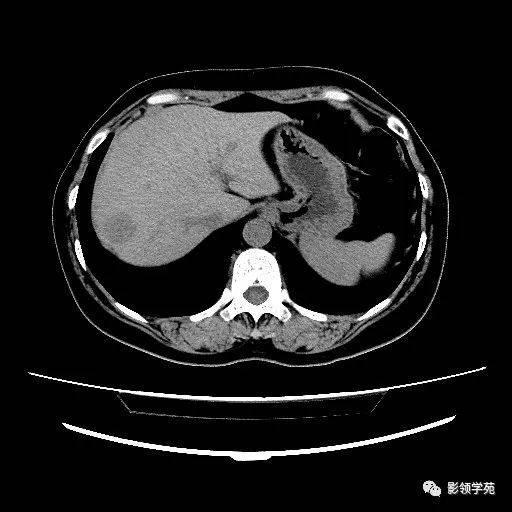

ct示:左肝内叶转移瘤!

图片尺寸780x1052